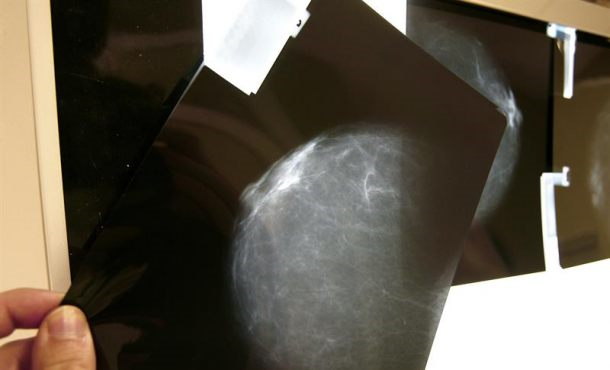

Agencias – El cáncer de mama sigue siendo el tumor femenino más frecuente y la primera causa de muerte por cáncer en mujeres de la Unión Europea. Para abordar este problema, la Consejería de Sanidad puso en marcha en 1992 el Programa gallego de detección precoz del cáncer de mama (PGDPCM) que acaba de cumplir 25 años. Santiago de Compostela (España), domingo 3 de septiembre de 2017. Fotografía: En la imagen, una prueba radiológica de mama. Archivo Efe.

La lectura de las mamografías se realiza por dos radiólogos de manera independiente en las unidades de evaluación radiológica. Esta doble lectura aumenta la sensibilidad de la prueba y la detección de los tumores más pequeños, los que miden menos de un centímetro.